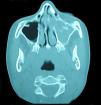

A la exploración presentaba dolor a la palpación sinusal maxilar y etmoidal izquierda, sin eritema de la piel, con movilidad ocular y agudeza visual normales. Se solicitó valoración al servicio de ORL que realizó una endoscopia nasal en la que se objetivó drenaje purulento espeso abundante por ostium maxilar izquierdo. Dado lo prolongado de la clínica con la exacerbación actual, los hallazgos exploratorios y la falta de respuesta a los tratamientos pautados, se solicita una TC de fosas y senos paranasales, en la que se observa una pansinusitis izquierda con ocupación completa del seno maxilar, complejo osteomeatal, celdillas etmoidales, seno frontal y esfenoidal izquierdos, con ocupación completa también del meato medio y superior izquierdos (fig. 1). Dentro del seno maxilar izquierdo se apreciaban imágenes de distintas radiodensidades (fig. 2).

La TC es la mejor prueba de imagen ya que permite observar la opacificación total o subtotal del seno afectado, en ocasiones con imágenes de esclerosis ósea de las paredes sinusales, objetivándose en el interior del seno diferentes radiodensidades, que corresponden a microcalcificaciones o hifas densas. Se debe recurrir a la RM si existe sospecha de invasión craneal o intraorbitaria10.